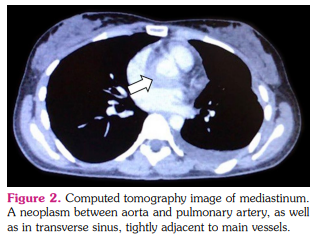

A 25-year-old female patient presented to a rheumatologist with complaints of severe weakness, shortness of breath with mild physical exertion, palpitations, low-grade fever in the evening, tightness of the chest, and weight loss by 6 kg within the past four months. She reported that she felt herself ill for six months. Initial complains were shortness of breath, fever, and pressure pain behind the sternum. The patient consulted a cardiologist, and echocardiography revealed a neoplasm in the anterior mediastinum (Figure 1). The hypodense structure without clear contours, semicircular in the circumference of the non-coronary and left coronary sinus of the aorta, spreading and circularly enveloping the mouth of the left coronary artery, causing a narrowing of the lumen up to 70 to 80% was detected by intravenous contrast-enhanced computed aortography. A similar structure was identified along the pericardial layers in the circumference of the mouth of the pulmonary artery trunk (Figure 2). Due to the impossibility of the radical removal of the neoplasm to clarify the diagnosis, it was decided to perform a biopsy of the mass fragment. Stenting of the left coronary artery was performed. Laboratory test results were as follows: anemia (hemoglobin: 104 g/L); eosinophilia (relative numbers and absolute) 12%, 1.3-1.5x109 /L; erythrocyte sedimentation rate 53 mm/h, and C-reactive protein 31 g/dL. Detected serum immunoglobulin G4 (IgG4) in a high titer-1,030 mg/dL (normal range: 3 to 201 mg/dL). Antineutrophilic cytoplasmic antibodies to myeloperoxidase (ANCA-MPO) were in high titer: 5.2 AI. On multislice computed tomography (MSCT) of the thorax with bolus enhancement, the contrast was accumulated along the periphery and in both lungs with multiple ring-like foci, close to the density of “ground glass” appearance.